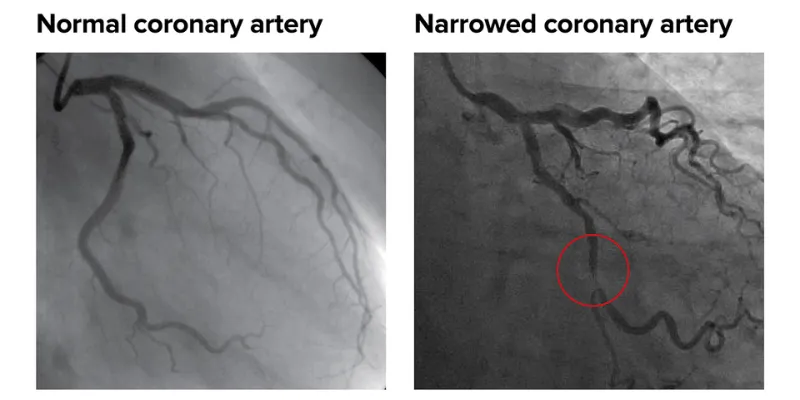

A coronary angiogram is an X-ray of the arteries in the heart. This shows the extent and severity of any heart disease, and can help you to figure out how well your heart is working.

The dye makes the blood flowing inside the blood vessels visible on an X-ray and shows any narrowed or blocked area in the blood vessel. The dye is later eliminated from your body through your kidneys and your urine.